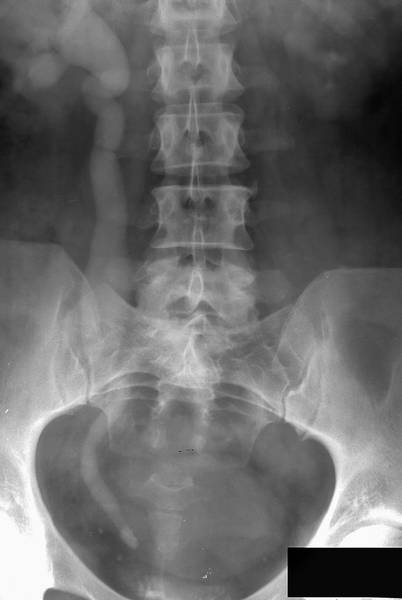

РЕТРОГРАДНАЯ УРЕТЕРОПИЕЛОГРАФИЯ

Ретроградная уретеропиелография впервые выполнена в 1906 г. Voelcker и Lichtenberg. Метод основан на получении теней ВМП после их ретроградного заполнения контрастным веществом (рис.).

Ретроградная уретеропиелограмма слева: тень мочеточникового катетера в проекции мочевого пузыря и нижней трети мочеточника; в лоханке — дефект наполнения округлой формы с ровными чёткими контурами, обусловленный рентгенонегативным камнем.

Для этого применяют жидкие (амидотризоевая кислота, йогексол) и газообразные (кислород, углекислый газ) контрастные вещества. По мочеточниковому катетеру вводят от 2 до 5 мл жидкого контрастного препарата. Если при этом у больного возникает боль или неприятные ощущения в области почки, то следует прекратить дальнейшее его введение и сделать рентгеновский снимок. Лучше проводить это исследование под рентгентелевизионным контролем. Ретроградную уретеропиелографию следует выполнять с одной стороны, а если есть показания, — то и с другой, но не одновременно. При макрогематурии ретроградную уретеропиелографию применять не рекомендовано, так как сгустки крови могут давать дефекты наполнения и быть ошибочно приняты за опухоль или конкремент.

В норме на уретеропиелограмме тень мочеточника располагается по латеральному краю поперечных отростков поясничных позвонков в виде тонкой полосы шириной 3–5 мм.